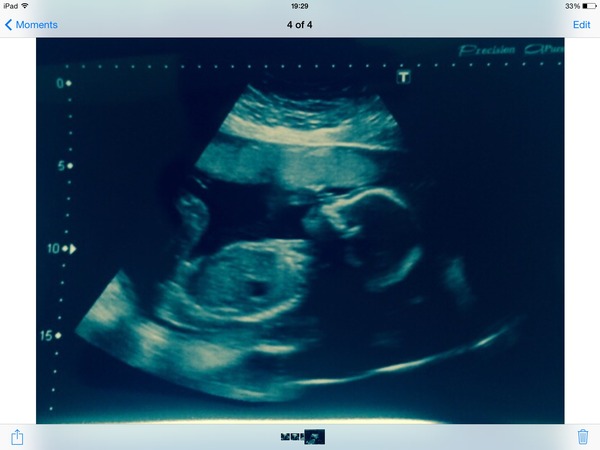

We had our 20 week scan and it showed a healthy baby boy

I am so shocked (nub theory said girl) and delighted. It's still sinking in. I feel so lucky, one of each, DH can have the snip now